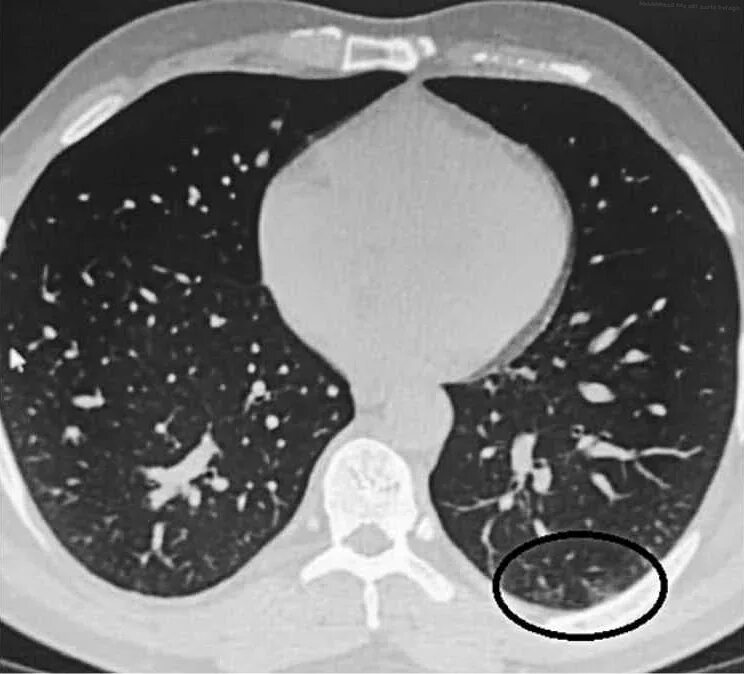

Заболевание кт